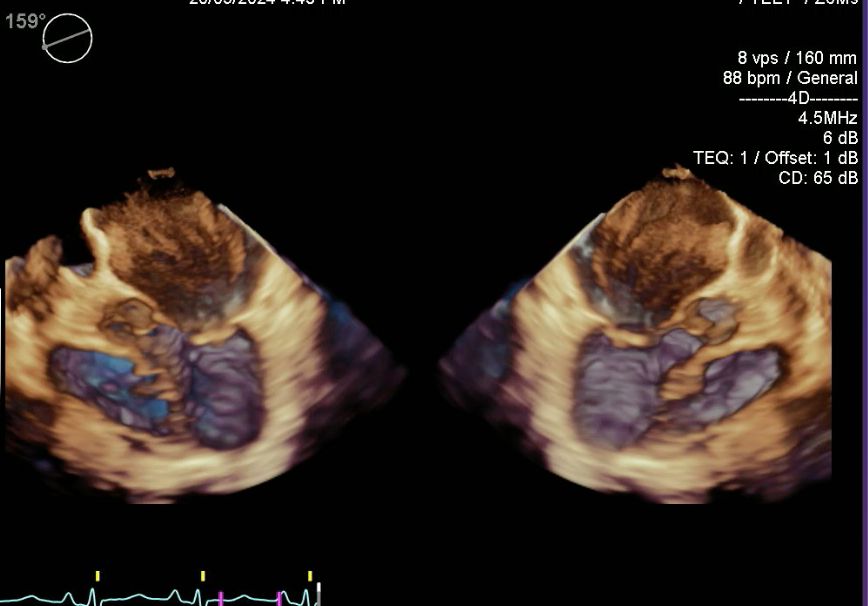

• Ecocardiografía

• Ecocardiograma

• Centro de Especialidades Médicas y Odontológicas Ecocardiograma  •

• Star Médica Mérida Consultorio 526 Ecocardiograma + doppler color  •